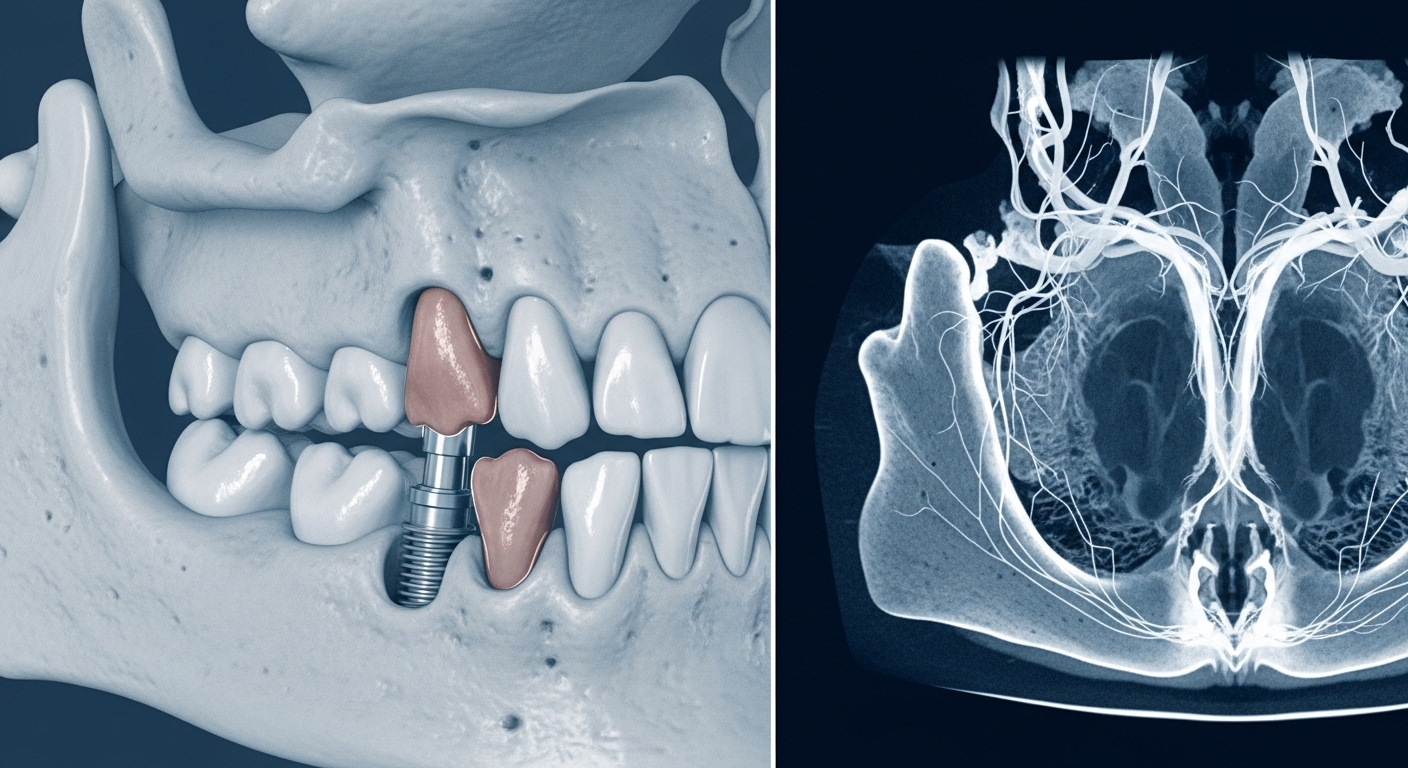

3D CT 촬영으로 정밀하게 진단된 구강 내부와 부족한 잇몸뼈를 보여주는 이미지입니다.

- 3D CT 촬영: 일반 엑스레이로는 잇몸뼈의 폭이나 밀도 등을 정확히 알기 어렵기 때문에, 3차원 CT 촬영이 필요합니다. 이는 신경이나 혈관의 위치를 파악하고 잇몸뼈 상태를 정밀하게 분석하는 데 사용되며, 보통 수만 원에서 10만원대까지 발생합니다.